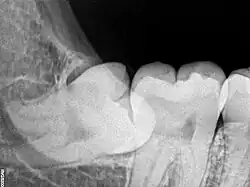

Risk factors of inferior alveolar nerve damage

Temporary and permanent inferior alveolar nerve (IAN) damage is a known complication of the surgical removal of impacted lower third molars, happening in 1 in 85 patients and 1 in 300 extractions, respectively. Studies have shown that certain risk factors may increase the likelihood of IAN damage. Proximity of the impacted third molar root to the mandibular canal, which can be seen in radiographs, has been shown to be a high-risk factor for IAN damage. Alongside this, the depth of impaction of the tooth, surgical technique and surgeons experience are all contributing risk factors for IAN damage during this procedure. Careful case-by-case consideration is crucial to avoid this risk.[44]